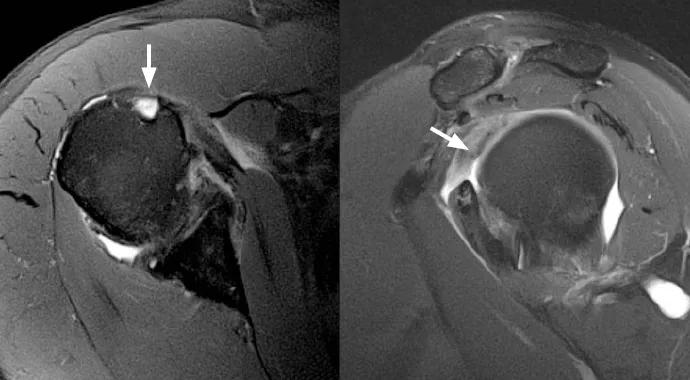

A routine noncontrast MRI examination was performed on a 3-tesla MRI machine (Siemens Verio®) using multichannel surface coils over the affected shoulder. The images demonstrated absence of the long head biceps tendon at the level of the bicipital groove without evidence of tendon dislocation, findings compatible with a complete tear with distal retraction (Figure 1). A sizable intra-articular remnant of the long head of the biceps tendon was still present and attached to the supraglenoid tubercle (Figure 2).

Figure 1 (left). MRI showing absence of the long head biceps tendon at the level of the bicipital groove with no evidence of tendon dislocation, which suggests a complete tear of the tendon with distal retraction. Figure 2 (right). MRI showing absence of the long head biceps tendon at the level of the bicipital groove with no evidence of tendon dislocation, which suggests a complete tear of the tendon with distal retraction.

The management of biceps tears is generally conservative in the absence of an intra-articular remnant. Surgical management may be required when an intra-articular fragment is present. For this reason, high-quality assessment of the intra-articular biceps is important diagnostically, as it can effectively alter the course of treatment. In this case, the patient was managed conservatively with NSAIDs and physical therapy and continues to report a gradual decrease in shoulder pain with time.

The 3-tesla MRI system has a magnetic field strength two to three times stronger than that of standard high-field systems, allowing acquisition of images at higher speeds and with much greater signal-to-noise ratios. In combination with multichannel coils, newer software and new imaging sequences, this allows for images with significantly higher resolution of small structures. This higher resolution enables more thorough evaluation of intra-articular structures. The result is greater diagnostic certainty and ultimately better patient care.